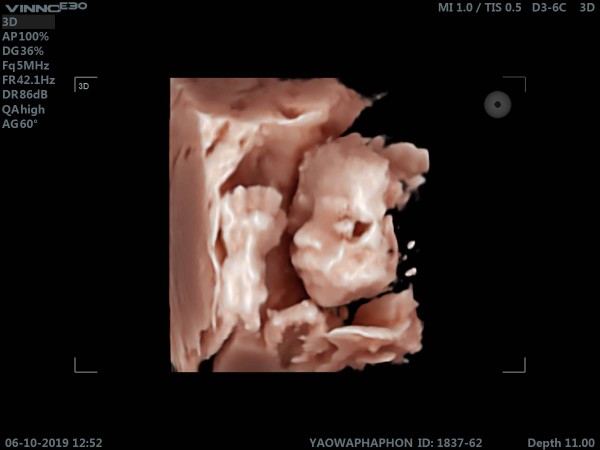

จมูกลูก

มีบ้านไหนซาวด์แล้วจมูกโด่งแบบนี้มั้ยคะ ออกมาจมูกน้องโด่งแบบนี้รึเปล่า? นี่คุณหมอบอกโด่งมาก?

17 w 2 d โด่งได้พ่อ ลูกครึ่งไทย-อังกฤษค่า

จมูกโด่งมากเลย มีชัยไปกว่าครึ้ง 555

ใบซาวด์ก้อโด่งค่า ตัวจริงก้อโด่ง

โอ้โหโด่งตั้งแต่ในใบซาวด์เลยค่ะ